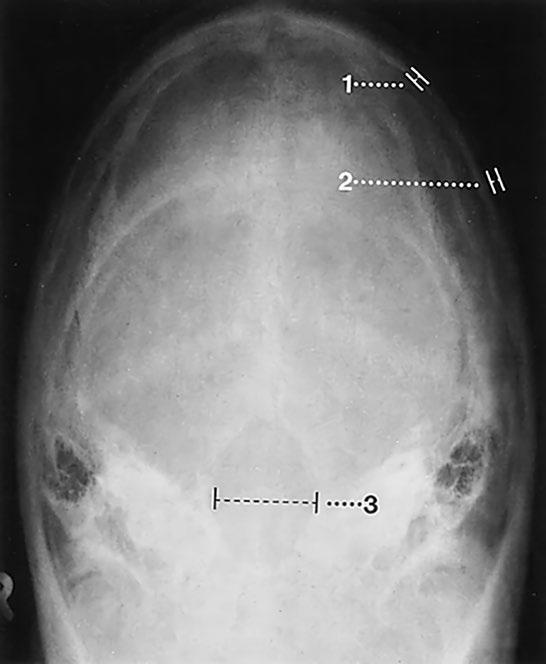

Týl, Towneova projekce

Zobrazené úseky lebeční kalvy jsou tvarem, tloušťkou a symetrií normální

Pravidelný průběh a věku odpovídající zobrazení lambdového a dalších zachycených švů Struktura a mineralizace kosti normální Kalva je hladká a ostře konturovaná bez patologických přerušení kontinuity nebo linií fraktur

Foramen magnum je tvarem, šířkou a ohraničením normální Nitrolebeční prostor nenápadný Normální zobrazení měkkých tkání

Závěr

Normální zobrazení týlu a foramen magnum

Kontrolní seznam

Tvar – symetrie

Švy – lambdový šev a úseky sagitálního švu: otevřené/zavřené (od 18 let)

– průběh pravidelný

– sklerotizace není zmnožená

– wormianské kosti (např incká kost)

Struktura – mineralizace

– ohraničení kostěných struktur ostré

– bez ohraničených projasnění nebo zhutnění (se sklerózou nebo bez ní)

– linie fraktur nejsou

– cévní kanály: arterie, diploické žíly, emissaria (průběh variabilní, nemusí být stranově srovnatelný, zhruba stejné uspořádání podle velikosti)

Kontury – lamina externa a interna hladké a ostré

– šíře (viz níže)

– bez přerušení kontinuity, bez schodovitých deformací

– exostózy nebo kostěné apozice nejsou

– periost není nadzdvižený

Foramen magnum – tvar (oválný, symetrický)

– šířka (viz níže)

– vnitřní kontury hladké, ostré

– bez schodů

Nitrolebeční prostor

– kalcifikace (pokud ano, lokalizace)

Měkké tkáně – intaktní

– bez otoku

– bez kalcifikací (lokalizace)

– bez cizích těles

Důležité údaje

(1) Šíře lamina interna: asi 0,5 mm

(2) Šíře lamina externa: asi 1,5 mm

(3) Šíře foramen magnum: asi 35 mm

(Cave: projekční chyba!)